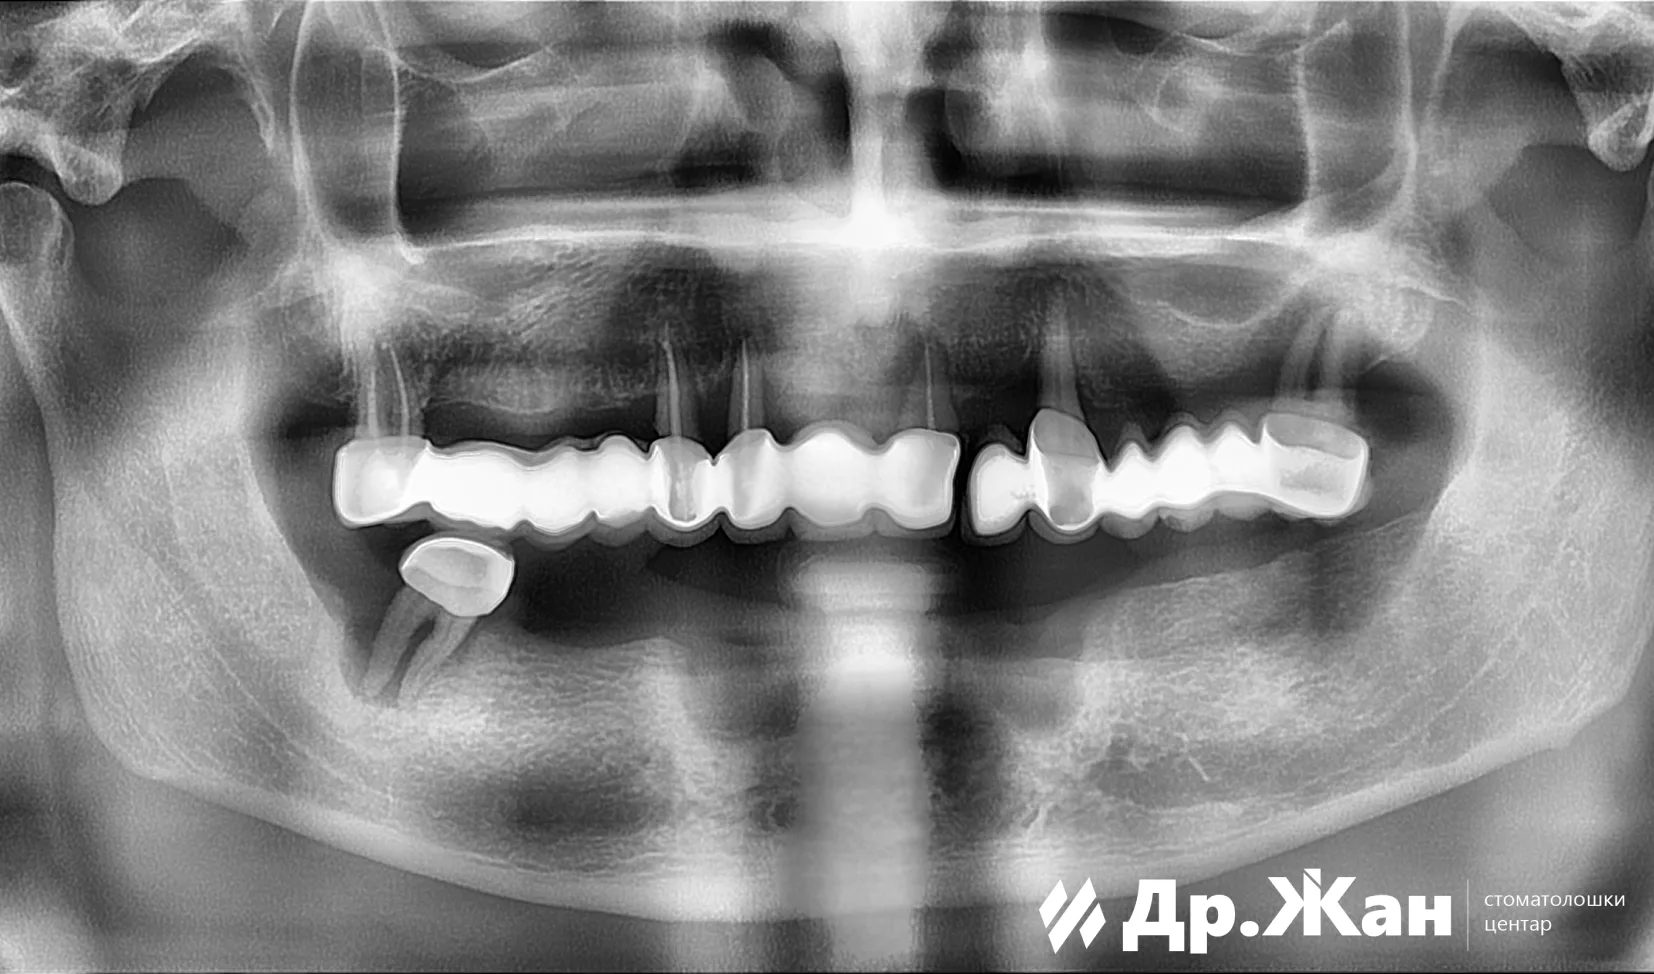

Овој господин дојде во нашата клиника со голем проблем. Имаше нефункционален металкерамички мост во горната вилица и нефункционална протеза во долната вилица. По првичниот преглед и томографијата, одлучивме дека на обете вилици им е потребно „All-on-6“ решение со забни импланти.

Користејќи компјутерски водена хирургија, поставивме 12 импланти во обете вилици и му обезбедивме на пациентот привремени заби за време на периодот на заздравување.